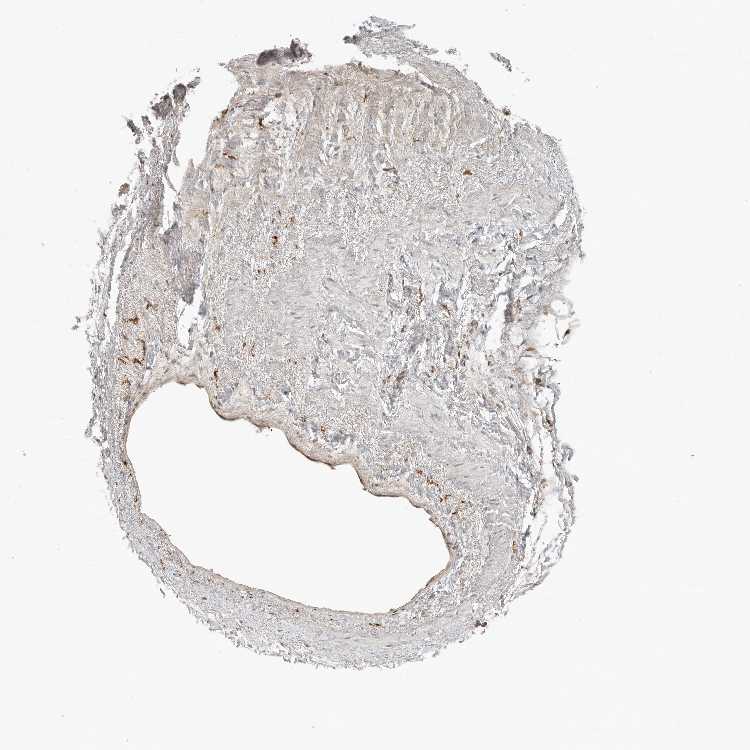

TISSUE PRIMARY DATA HEART MUSCLE Show tissue menu

HEART MUSCLE - Antibody stainingi

Antibody staining in the annotated cell types in the current human tissue is reported as not detected, low, medium, or high, based on conventional immunohistochemistry profiling in selected tissues. This score is based on the combination of the staining intensity and fraction of stained cells.

Each image is clickable and will lead to virtual microscopy that enables deeper exploration of all samples and also displays staining intensity scores, fraction scores and subcellular localization as well as patient and tissue information for each sample.

Antibody HPA024770Antibody HPA027115

Cardiomyocytes MediumLow